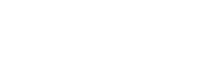

Su tratamiento consiste en extraer parcial o totalmente la pulpa dental que ha sido dañada o infectada para después rellenar ese espacio con diferentes materiales. El objetivo es devolver la funcionalidad al diente y acabar con el dolor provocado por la pulpitis.